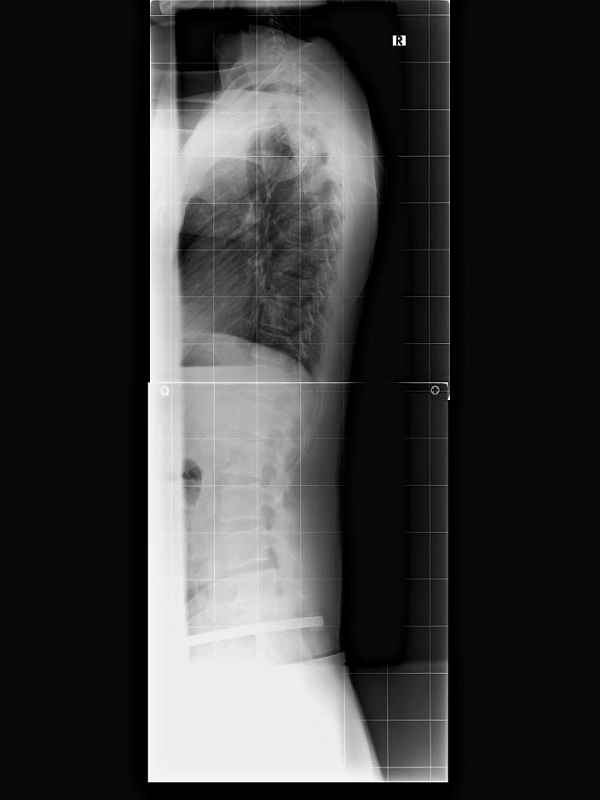

Ich habe mal Röntgenbilder reingestellt.

Aus meiner Sicht würde ich das so beschreiben:

- (doch) kein starkes LWS Kyphose Problem

- die unterste Bandscheibe ist recht stark abgenutzt.

Nach Dr. Hoffmann kommt das durch die verkürzte Rückenmuskulatur

Interessant sind die 'Haken' die am ersten Wirbel wachsen. Hier versucht der Körper auszugleichen, was langfristig zu einer Versteifung an dieser Stelle führen könnte.

Ich habe auch einen Beckenschiefstand oder meine Beine sind unterschiedlich lang, in der Aufregung weiß ich es nicht mehr genau. Der Beinlängenausgleich (rechts höher stehen als links) brachte aber keine bessere Stabilität für die Wirbelsäule. Ich sollte nach Dr. Hoffmann also keine unterschiedlich hohen Schuhe tragen.

Interessant war auch, dass meine Hüftgelenke nicht richtig in der Pfanne sitzen. Normal ist 120 Grad, ich habe aber 160 (der rote Pfeil im 1. Bild: ganz verstanden habe ich das nicht, ob von hinten oder von der Seite gesehen? Muss ich nochmal nachlesen bzw. ne Quelle finden). 160 Grad haben Säuglinge. Da habe ich mich also als Kind auch nicht normal entwickelt. Dr. Hoffmann meinte, dass man das auch korrigieren könnte. Im Moment aber nicht notwendig, da ich keine Probleme mit Hüfte oder Leisten habe.